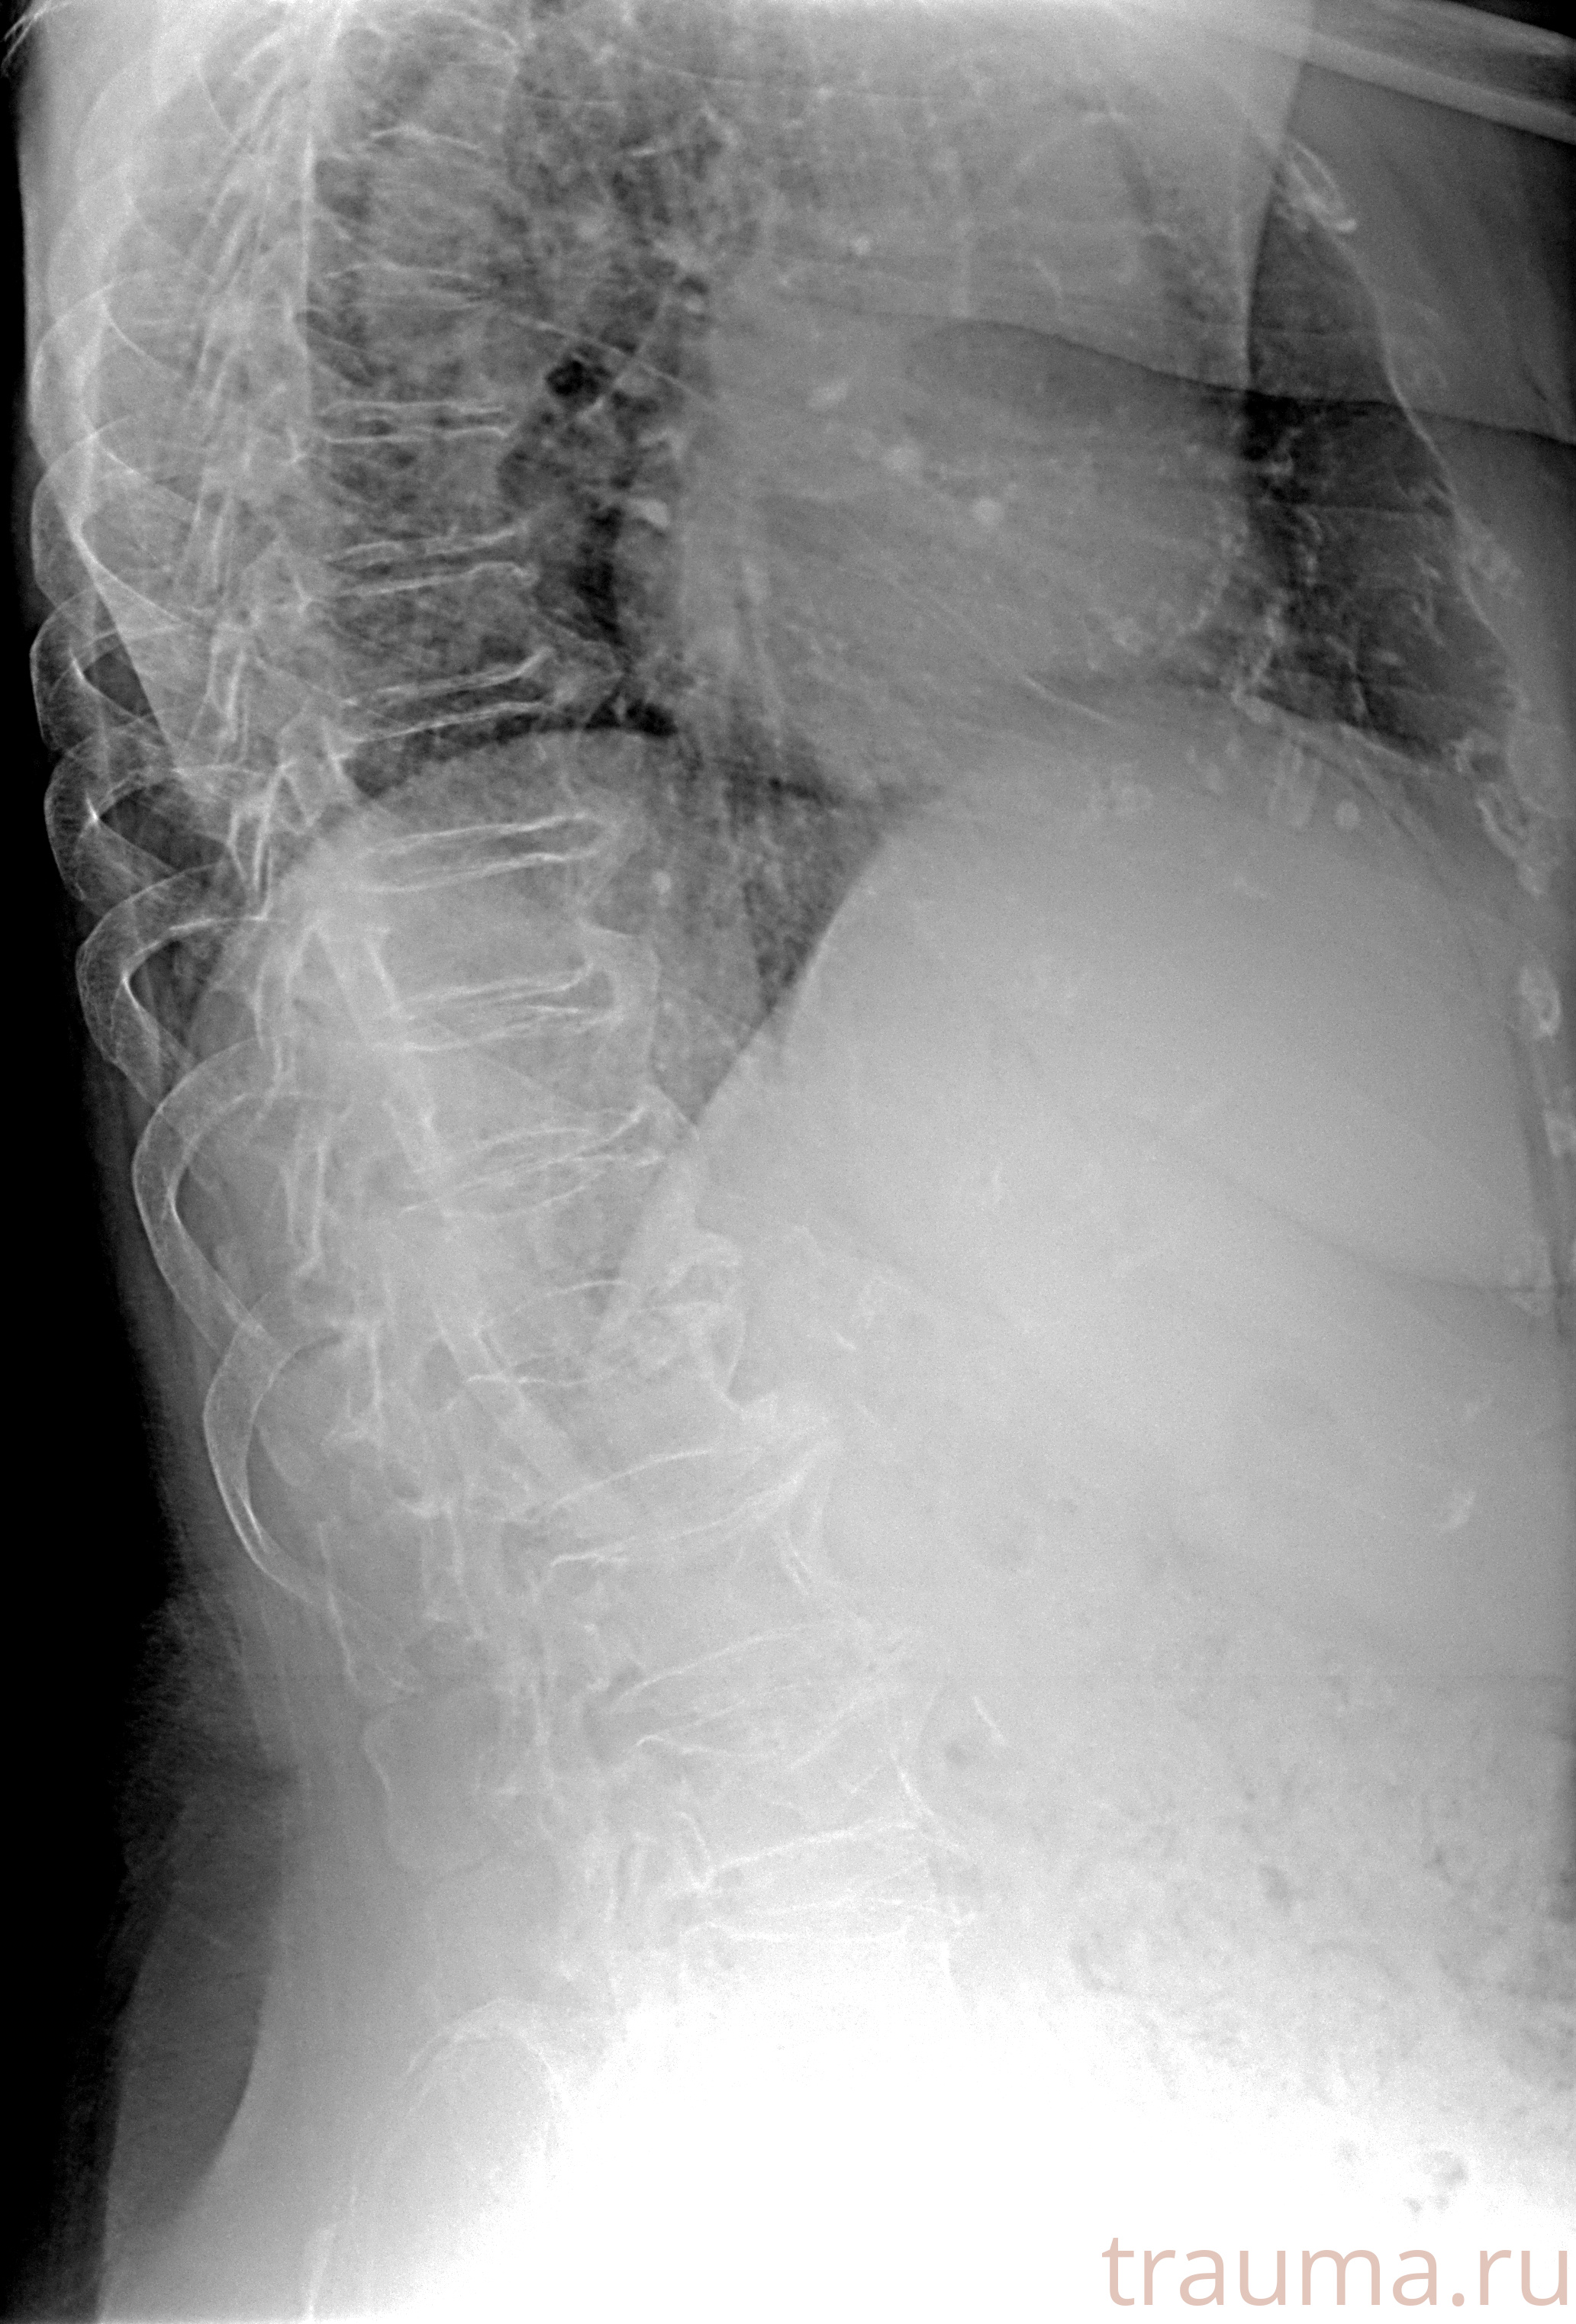

Рентгенограммы

Рентген на дому: по вашему адресу приезжает врач-рентгенолог, травматолог-ортопед с мобильным рентгеновским аппаратом, проводит диагностику травмы или заболевания, делает необходимые рентгенограммы, дает рекомендации по дальнейшему лечению. Получить качественные снимки в домашних условиях возможно благодаря уникальной методике, разработанной МосРентген Центром для института  Склифосовского

при переломе шейки бедра и пневмонии от компании МосРентген Центр - партнера Института имени Склифосовского